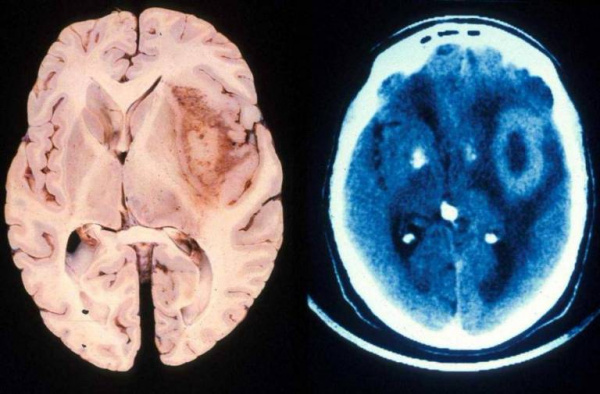

2. КТ при глиобластоме:

• Бесконтрастная КТ:

о Неравномерно изоденсное или гиподенсное объемное образование с гиподенсной центральной частью, отражающей некроз

о Выраженные масс-эффект и перифокальные отек/опухолевая инфильтрация

о Нередко геморрагический компонент

о Редко каьцификация (связана с дегенерацией опухоли низкой степени злокачественности)

• КТ с контрастированием:

о Высокоинтенсивное гетерогенное неравномерное кольцевое контрастирование

Опухоль головного мозга — глиобластома. Компьютерная томография (КТ). Синяя звездочка в центре обозначает зону центрального некроза опухоли, заполненную жидкостью. Желтые стрелки — окружающий мягкотканный компонент опухоли. Красные звездочки — перифокальный отек мозга. Наблюдается смещение срединных структур и угроза нисходящего транстенториального вклинения мозга.

Проявления опухоли на КТ-сканах без контрастного усиления включают неоднородное образование с нечеткими краями; внутренние области низкой или жидкостной плотности являются очагами некроза (представлены более, чем в 95% МФГ); внутренние области высокой плотности, являющиеся очагами геморрагии или, реже, кальцификациями (они более характерны в тех случаях, когда МФГ является результатом трансформации из астроцитомы низкой степени злокачественности); и значительный масс-эффект и отек (возогенная природа отека).

Исследование КТ с контрастным усилением значительно увеличивает выявление таких признаков, как неровные контуры образрвания, неоднородность, возможное кольцевидное контрастное усиление в периферических отделах патологической зоны.

- Компьютерная томография. Выявляет изоденсное церебральное образование с гиподенсным участком центрального некроза, перифокальным отеком, геморрагическим компонентом. Характерен масс-эффект. КТ с контрастированием демонстрирует кольцевое неравномерное окрашивание. Микроскопическая инфильтрация обычно распространяется за пределы визуализируемого очага.